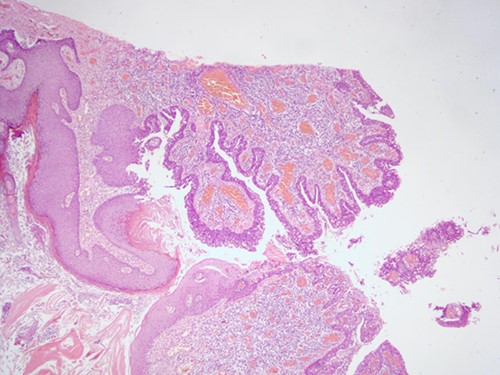

The histopathological examination found cystic invaginations of the infundibular epithelium projecting into the dermis, covered by a double cell layer (Fig. 2), proliferation of glands with prominent papillary architecture (Fig. 3) and fibrous cores containing numerous stromal plasma cells (Fig. 4). Other findings include verrucous (papillomatous) epidermal hyperplasia with hyperkeratosis and hypergranulosis (Fig. 5), irregular duct-like structures and cystic spaces (Fig. 6) and glands with double layer of cuboidal columnar epithelium and numerous stromal plasma cells (Fig. 7). These findings are compatible with Syringocystadenoma papilliferum with no signs of malignancy.

H&E staining, 4× magnification. Verrucous (papillomatous) epidermal hyperplasia with hyperkeratosis and hypergranulosis.